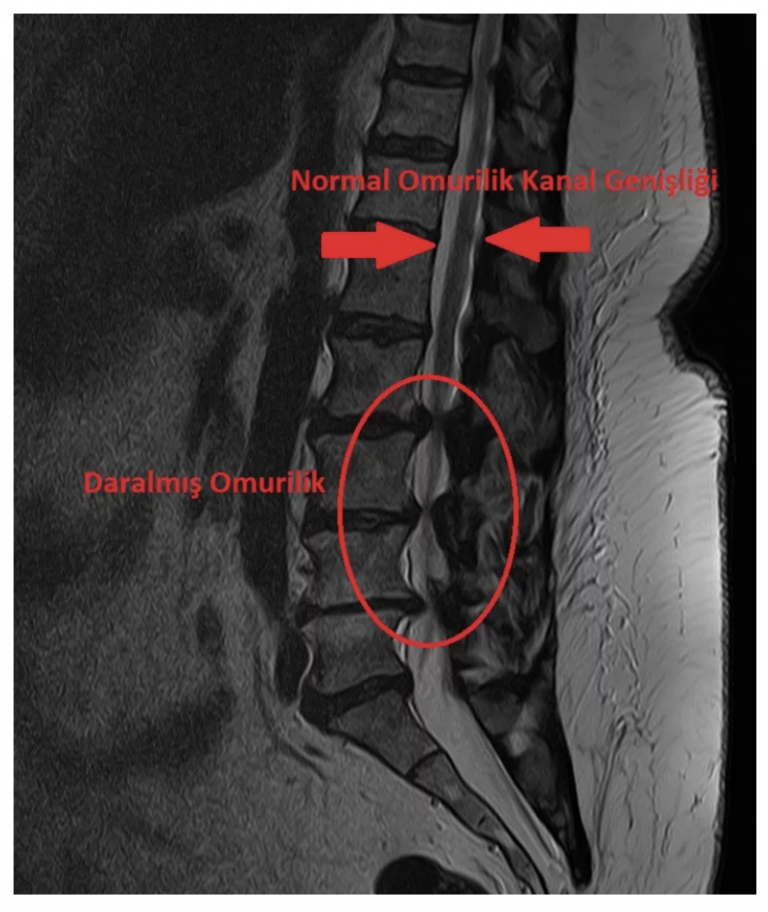

Omurilik kanalı daralması, omurların hemen arkasında yer alan omurilik kanalının çepeçevre daralarak, yukardan aşağı içinden geçen omuriliği çeşitli seviyelerde sıkıştırması ve beraberinde de sinir köklerine yaptığı basıya denir. Bel omurilik kanalı daralması dejeneratif bir süreçtir. Bu sürece yukarıda sayılan tüm yapıların dejeneratif değişimleri katkıda bulunur ve hasta bir süre sonra dar kanal sorunu ile karşı karşıya kalabilir. Omurlar arası disklerin yaşlandıkça su içeriğinin azalması, faset eklemlerin içe doğru büyümeleri, omurlar arkası bağın kalsifiye olarak (kireçlenerek) omuriliği önden, omurilik arkasında yer alan sarı bağın kalınlaşarak arkadan bası yaratması bel omurilik kanalı daralmasında ana etkenlerdir (Resim 2).

Belde omurilik kanalı daralması, yavaş gelişen bir süreçtir. Bu nedenle ilk başta şikayetlere ve bulgulara neden olmayabilir. Ancak hastalık ilerlediğinde hastaların yaşam kalitesi bozulur, günlük aktiviteleri belirgin derecede kısıtlanır. Hastalarda bu klinik tablo ortaya çıktığında çoğunlukla omurilik kanal çapı belli bir derecenin üzerinde daralmış, omurilik ve ondan çıkan sinir kökleri sıkışmış, durumdadır.